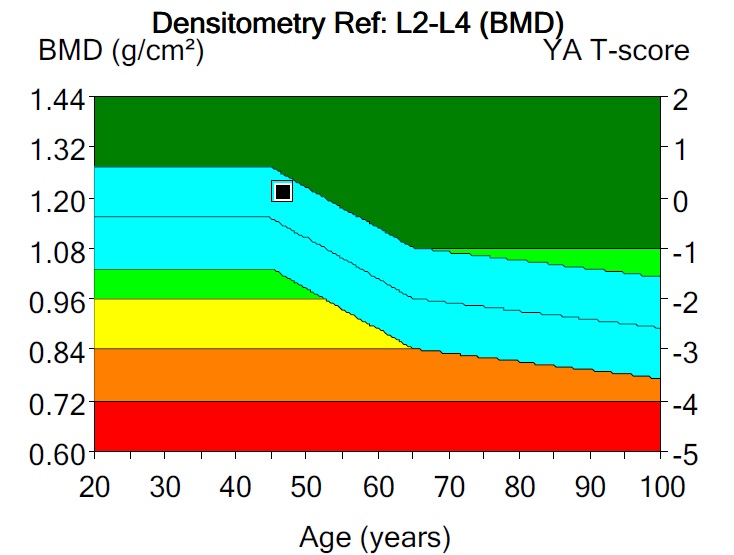

Bone Mineral Density BMD Osteoporosis Dual Energy X ray Absorptionmetry

Bone Mineral Density Radiology World